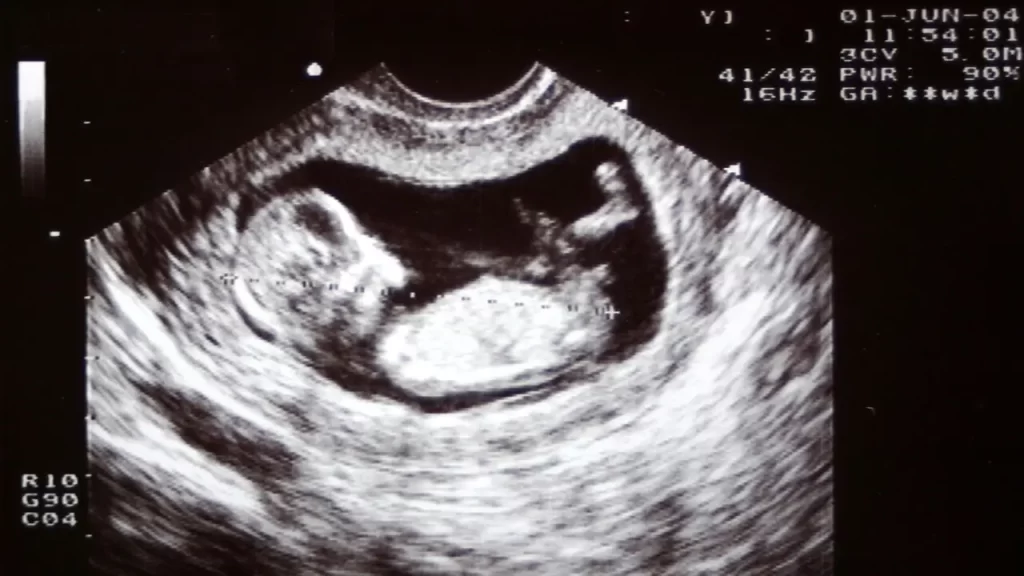

عکس سونوگرافی جنین در هفته نهم بارداری